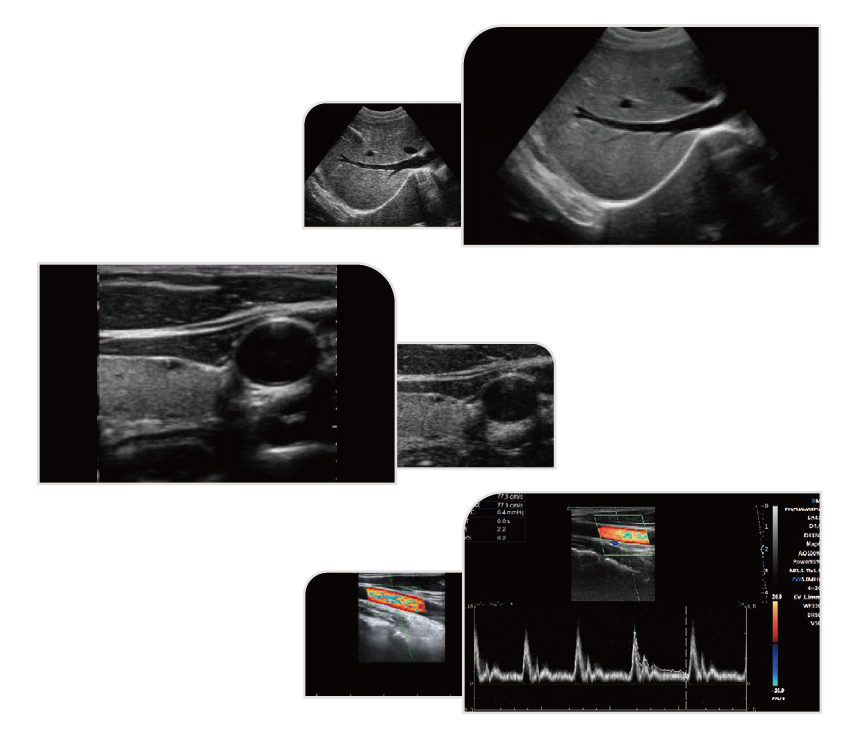

- Imagistică Trapezoidală

Oferă un câmp de vizualizare mai larg decât imaginile standard dreptunghiulare. Permite evaluarea unei zone anatomice extinse într-o singură scanare.

- Imagistică Compozită Spațială

Îmbunătățește rezoluția de contrast și claritatea detaliilor fine. Reduce artefactele precum speckle, reflexii și atenuări. Asigură contururi tisulare mai bine definite.

- Tissue Harmonic Imaging (THI)

Crește contrastul imaginii și reduce zgomotul. Oferă delimitare mai precisă a leziunilor. Îmbunătățește calitatea imaginii la pacienți cu dificultăți imagistice.

- Tehnologie Micron Imaging

Optimizează detecția marginilor și a structurilor fine. Îmbunătățește contrastul imaginii bidimensionale. Permite analiză detaliată a informației interne a pixelilor.

- Doppler cu Auto-Envelope

Calculează automat parametrii hemodinamici. Determină frecvența cardiacă și indicele de rezistență. Oferă evaluare vasculară rapidă și precisă.